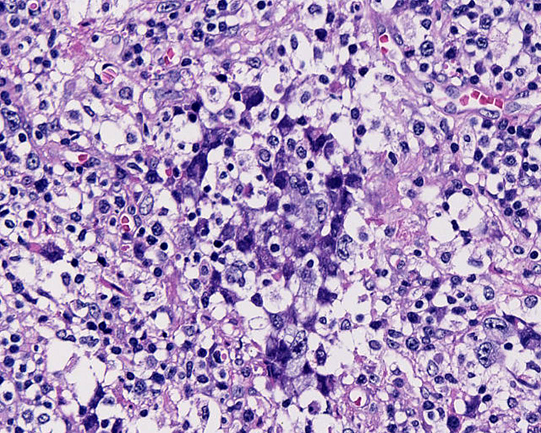

リンパ節組織所見

HE NZX10HE NZX40HE NZX40

大型異型細胞が集簇し結合性に増殖している。未分化癌や悪性黒色腫が鑑別となる。細胞は大型で類円形, 楕円形核に加えて腎臓様の特異な核形を示す。